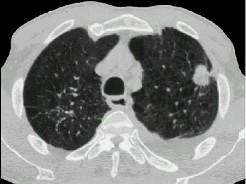

问题 女,64岁,胸背疼痛一周,CT检查如图,最可能的诊断为 ( )

选项 A、右上肺单发性转移癌 B、右上肺错构瘤 C、右上肺周围型肺癌 D、右上肺炎性假瘤 E、右上肺结核球

答案 C